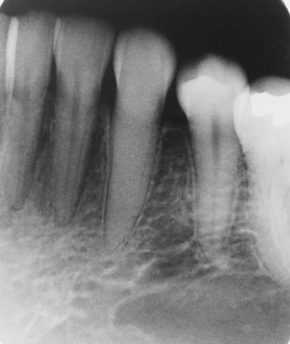

which tooth is nonvital

24

23

22

21

What is seen on the premolars in this image?

toothbrush abrasion

abfractions

cervical caries

cervical restorations